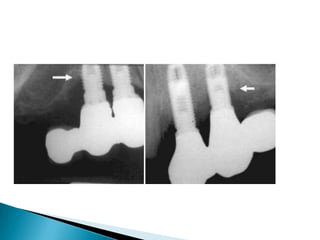

 Single toothimplants in posterior quadrants ◦ Maxilla Vs mandible ◦ In mandibular first molar - conventional diameter 3.75 or 4.0 mm - unfavorable results ◦ When external hex-headed implants were used – loosening of the screw because the diameter of the implant head is much smaller than the size of the occlusal surface. Tipping of restoration – leads to stretching and loosening of the screw

Single-tooth restoration inthe posterior mandible supported by a wide- diameter implant. A, Clinical photograph of healing abutment on wide-diameter implant. B, Photograph of laboratory model with single molar. C, Clinical photograph of molar crown supported by wide-diameter implant. The use of wide-diameter (external hex) implants eliminates the problem of screw loosening for single-tooth, posterior, implant-supported crowns.